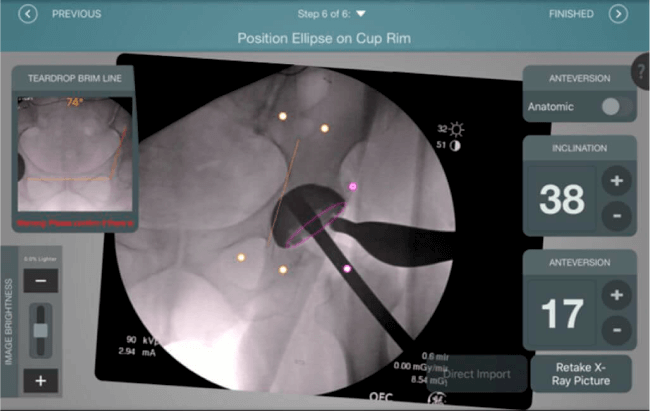

Mayor nivel de información intraoperatoria facilita la colocación correcta de los implantes:

• Inclinación y anteversión de la copa acetabular para una correcta colocación del implante.

• Desplazamiento y offset para posicionamiento óptimo del componente (vástago) femoral.

• Verificación de la posición deseada del implante que potencialmente puede ayudar a reducir la probabilidad de dislocación protésica y aumentar la estabilidad de la articulación.

• Anotaciones digitales y herramientas de análisis de longitud de pierna.

• Con tecnología ONETRIAL® que calcula automáticamente el cambio en la longitud de la pierna y el desplazamiento para todas las combinaciones de implantes en una tabla fácil de leer.